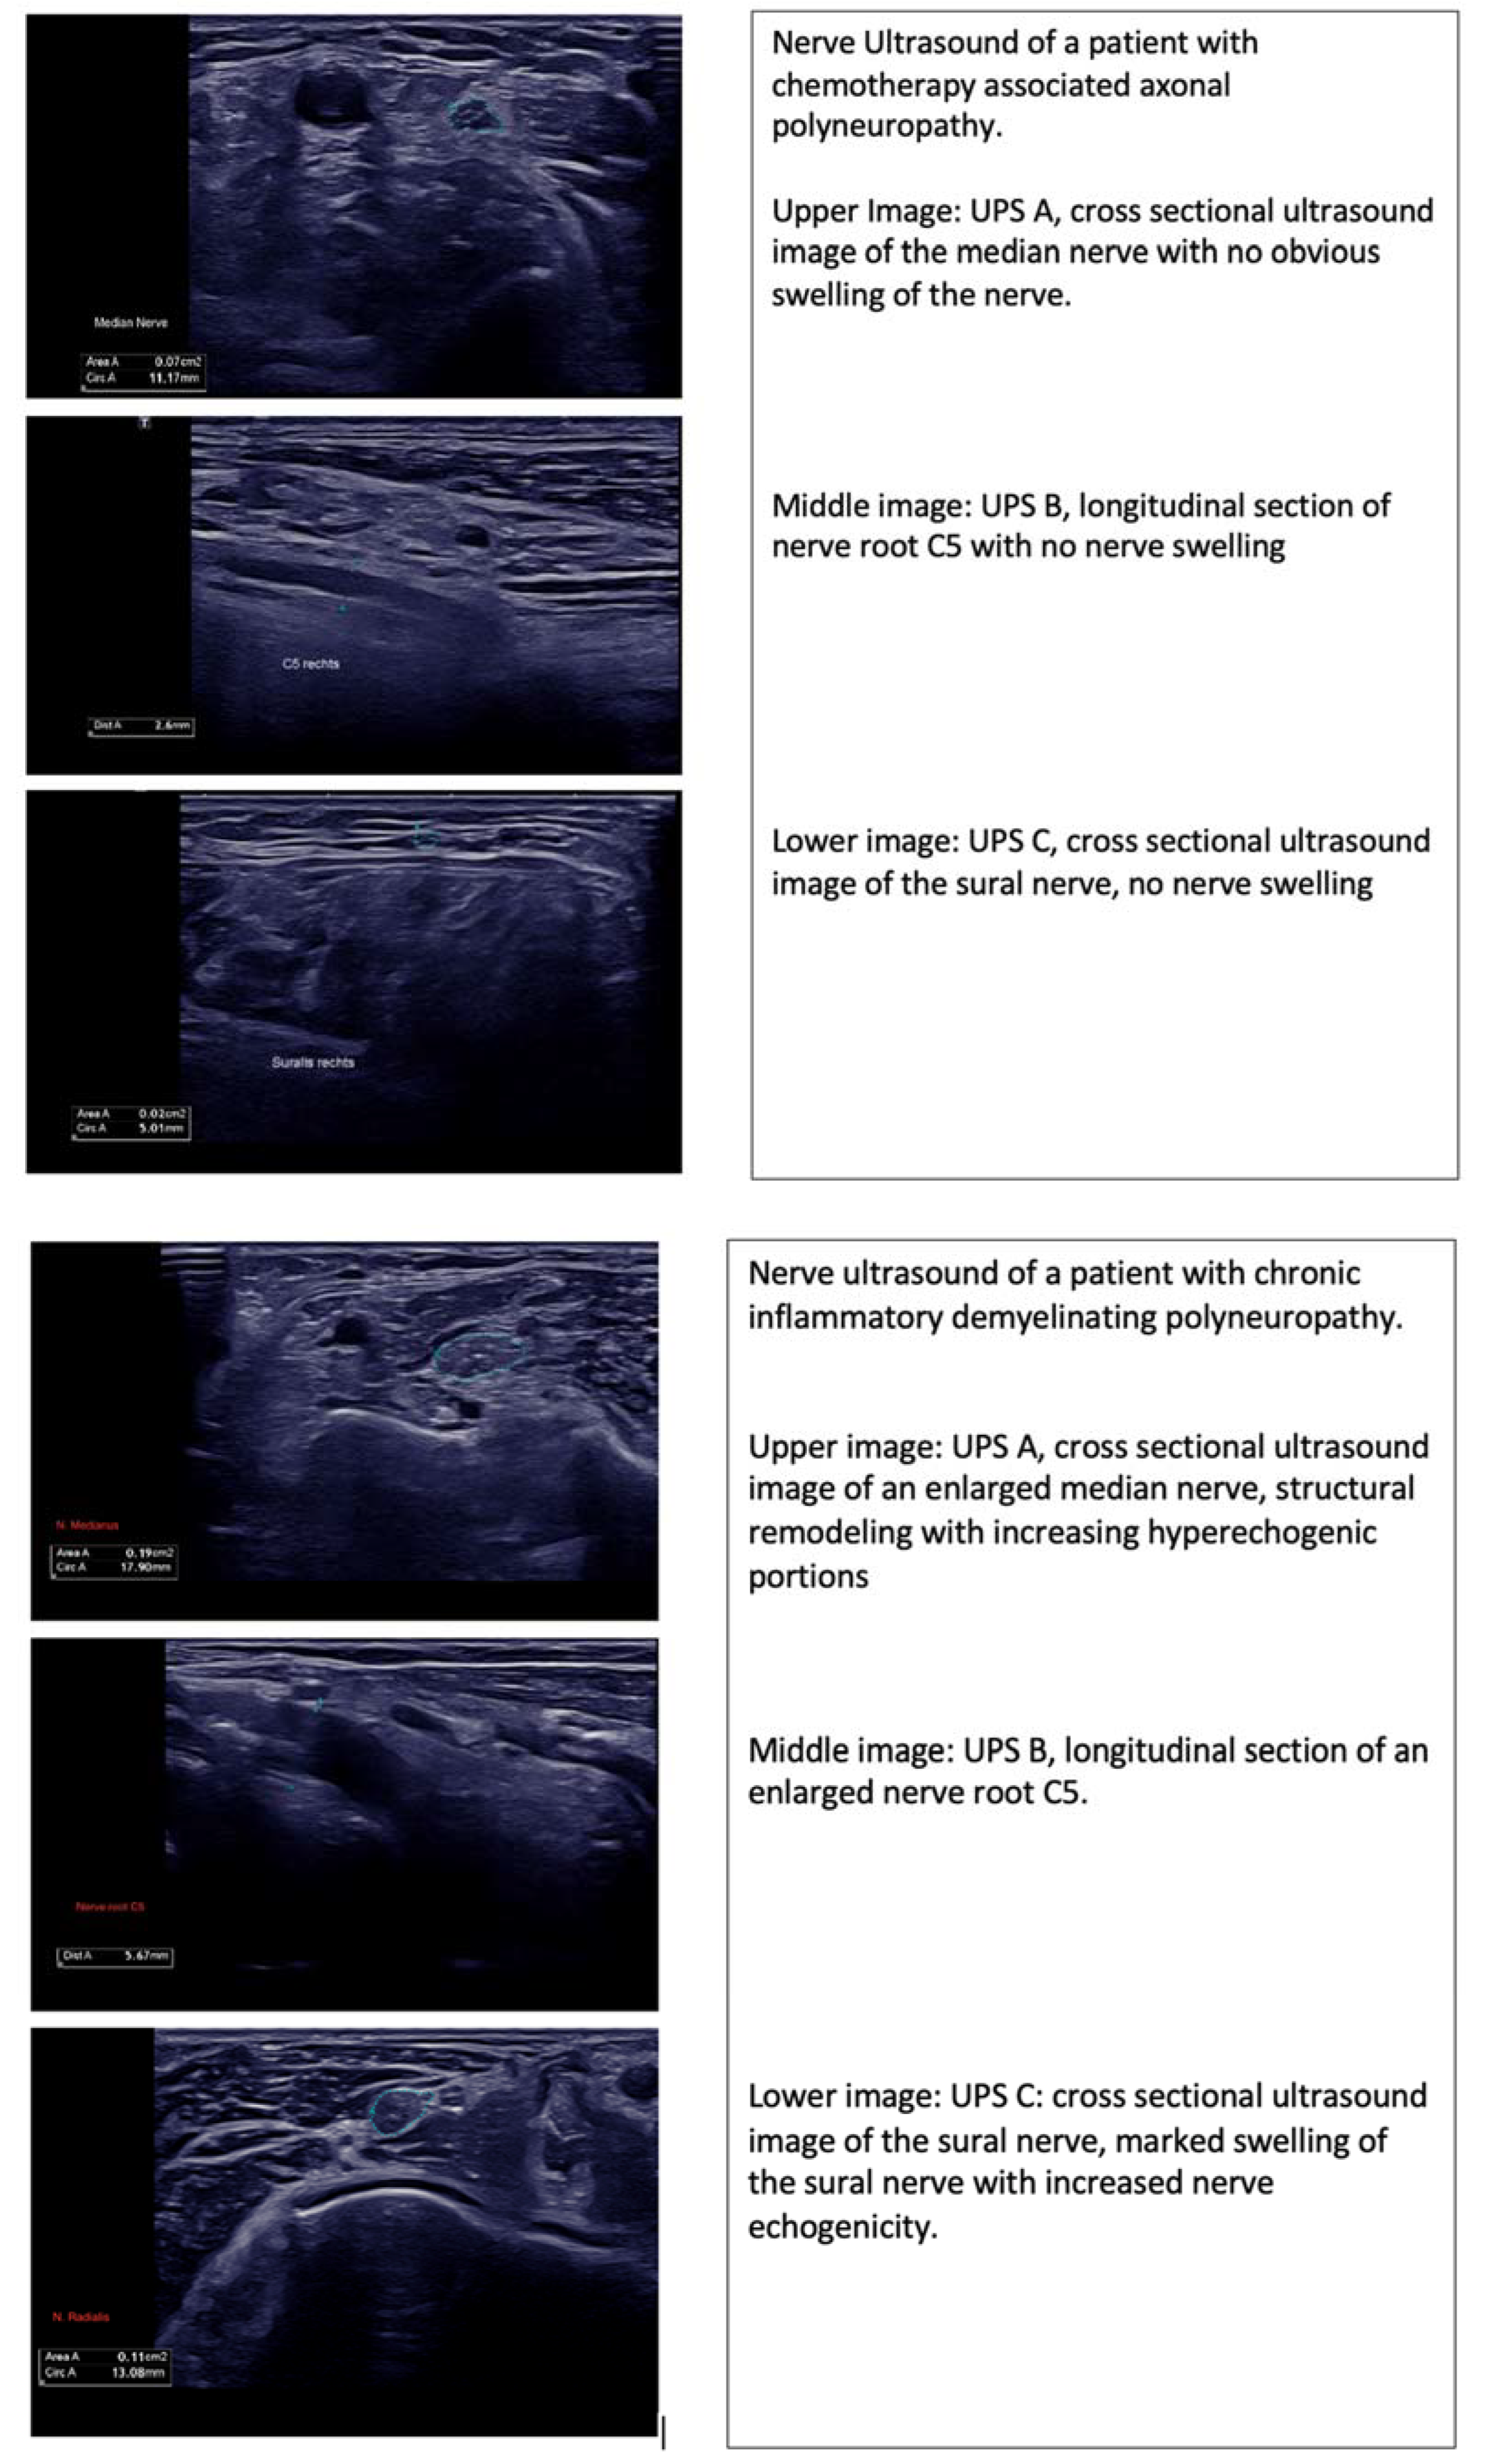

In our patient collective, 60% of cases showed nerve swelling, which was inhomogenic and did not solely affect the peripheral sensorimotor nerves (UPS A), but also affected the C5/6 nerve roots, vagus nerve (UPS B) and sensory nerves (UPS C). In 20% of patients no nerve swelling was observed, and the UPSS obtained varied from 0 to 5. (Table 1, Figure 1).

Figure 1.

Nerve sonography data of (top) patient with immunotherapy-related adverse event; (middle) patient with chemotherapy-associated polyneuropathy; (bottom) patient with chronic inflammatory demyelinating polyneuropathy. Abbreviations: UPS A (Ultrasound Pattern Score A): peripheral sensorimotor nerves; UPS B (Ultrasound Pattern Score B): C5/6 nerve roots and vagus nerve; UPS C (Ultrasound Pattern Score): sensory nerves.

Nerve ultrasound in CIDP patients may reveal prominent single-fascicle swelling or increased intraneural echogenicity. The current data suggest that increased nerve echogenicity is associated with nerve structure remodeling, which is secondary to chronic inflammatory processes. Further, nerve swelling may affect all nerve segments, which was also found in our CIDP cohort. Compared to our CIDP patient collective, the nerve swelling observed in our nirAE patients was slight and not statistically significant, with p > 0.05. (Table 2, Figure 1). Although increased nerve swelling and, therefore, an increased UPSS is observed in patients with autoimmune-mediated polyneuropathies, there are exemptions to this as seen in sarcoidosis or vasculitis.